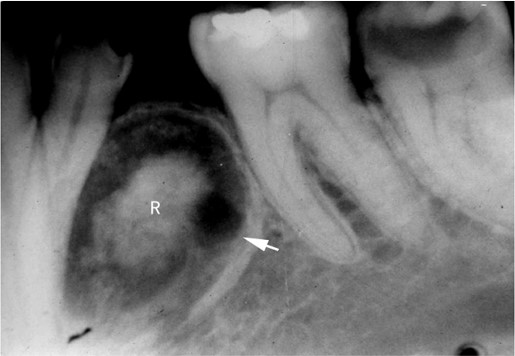

X线显示边界清楚、单房性透射影,常围绕一个阻生牙牙冠(图14.1-18),类似于含牙囊肿。

图14.1-18 牙源性腺样瘤(X线)